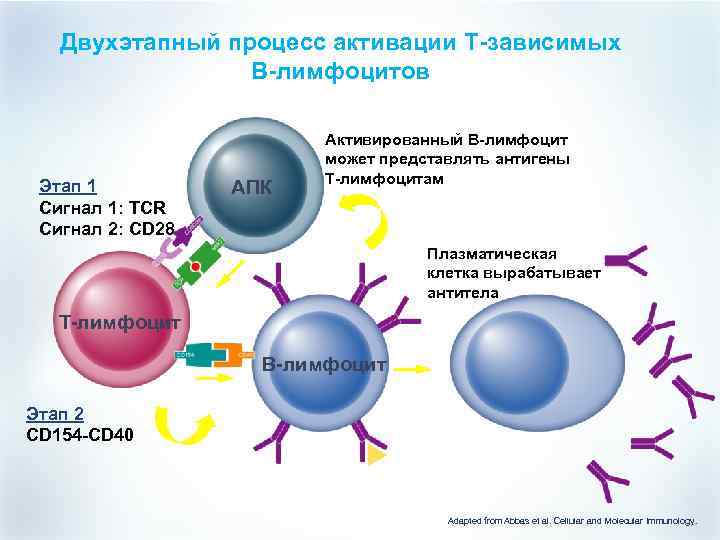

Двухэтапный процесс активации T-зависимых B-лимфоцитов Этап 1 Сигнал 1: TCR Сигнал 2: CD 28 АПК Активированный B-лимфоцит может представлять антигены T-лимфоцитам Плазматическая клетка вырабатывает антитела T-лимфоцит B-лимфоцит Этап 2 CD 154 -CD 40 ИЛ-4 Антиген Adapted from Abbas et al. Cellular and Molecular Immunology.

Двухэтапный процесс активации T-зависимых B-лимфоцитов Этап 1 Сигнал 1: TCR Сигнал 2: CD 28 АПК Активированный B-лимфоцит может представлять антигены T-лимфоцитам Плазматическая клетка вырабатывает антитела T-лимфоцит B-лимфоцит Этап 2 CD 154 -CD 40 ИЛ-4 Антиген Adapted from Abbas et al. Cellular and Molecular Immunology.